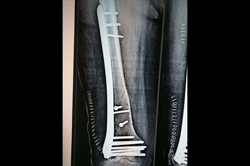

Tibia Nailing